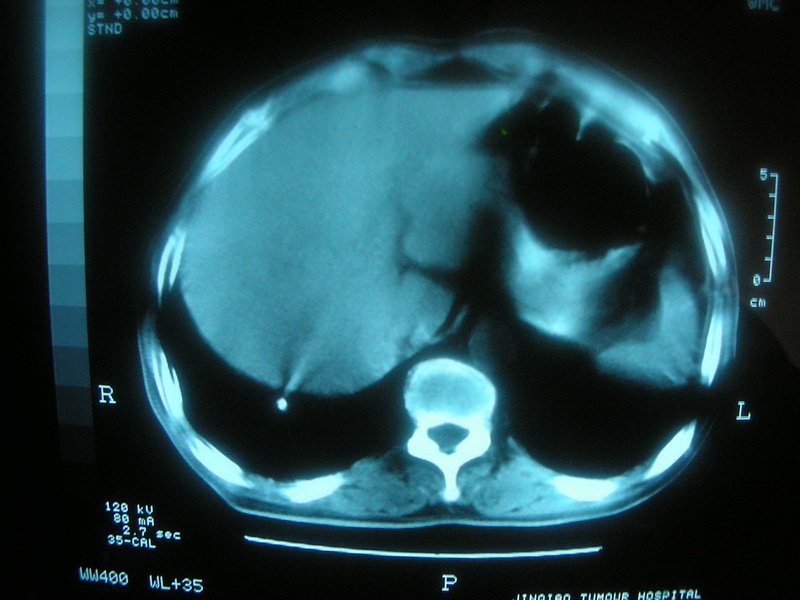

标题: CT11692:男,63岁,糖尿病史15年.抗炎治疗7天,病情 [打印本页]

标题: CT11692:男,63岁,糖尿病史15年.抗炎治疗7天,病情

请老师看看是结核还是炎症?

根据影像表现及临床符合结核感染。

双肺继发性肺结核伴感染!